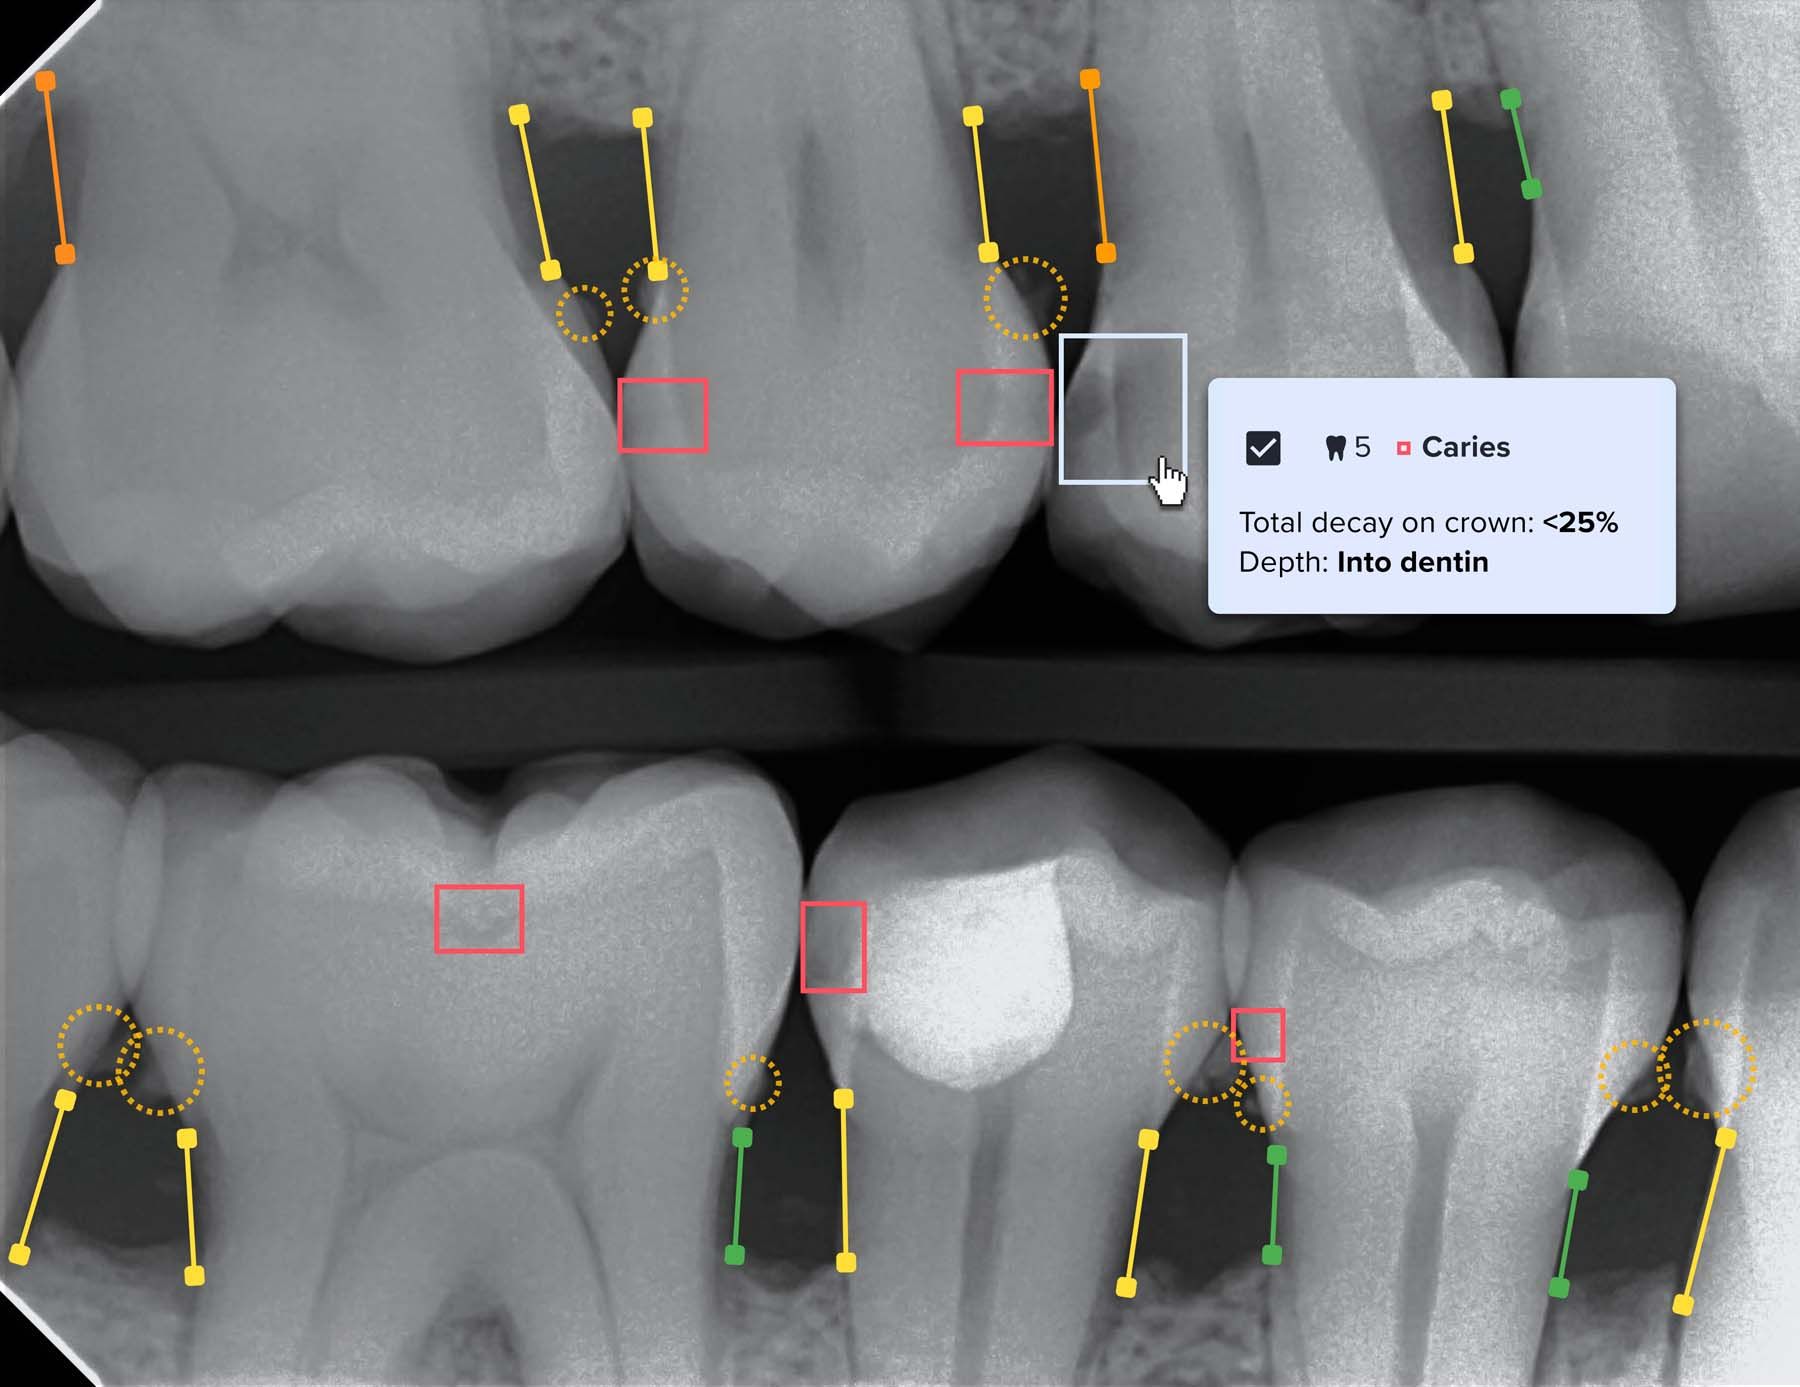

Videa Dental Assist uses AI technology to assist clinicians in diagnosing x-rays and in recommending treatment plans for patients. | Image Credit: © VideaHealth

VideaHealth, meanwhile, recently achieved a milestone with the FDA granting 510(k) clearance for its latest product, Videa Dental Assist. The clearance includes more than 30 AI algorithms, expanding AI detections to cover all the most common dental diseases, according to the company, which has partnered with the large dental support organization Heartland Dental.

“AI technology is revolutionizing dentistry by enhancing early detection and intervention for patients. From identifying routine issues like cavities to pinpointing more serious conditions such as periodontal disease or bone loss associated with illnesses like diabetes, dental AI technologies excel in reading x-rays and learning to discern areas of disease like decay, lesions, and bone loss,” says Heartland Dental Senior Vice President of Clinical Operations and Clinical Director Tim Quirt, DDS, MBA. “While AI empowers dentists with valuable insights, it is crucial to emphasize that it is not a replacement for doctors. It operates as a partner, allowing dentists to validate and strengthen their analyses, ensuring they maintain the ultimate decision-making authority over both diagnosis and treatment.”

VideaHealth’s Hillen predicts the technology will be used by most dental practices. “Using dental AI alongside dentists and hygienists will become the standard of care within the next 2 to 3 years,” he says. “We see that dentists supported by AI are more accurate, efficient, and able to diagnose issues sooner. And they can spend more time interacting with and evaluating their patients vs prioritizing x-ray analysis. AI is also becoming a competitive differentiator. Data shows patients are more open to taking action with an AI-validated diagnosis and are interested in practices using dental AI.